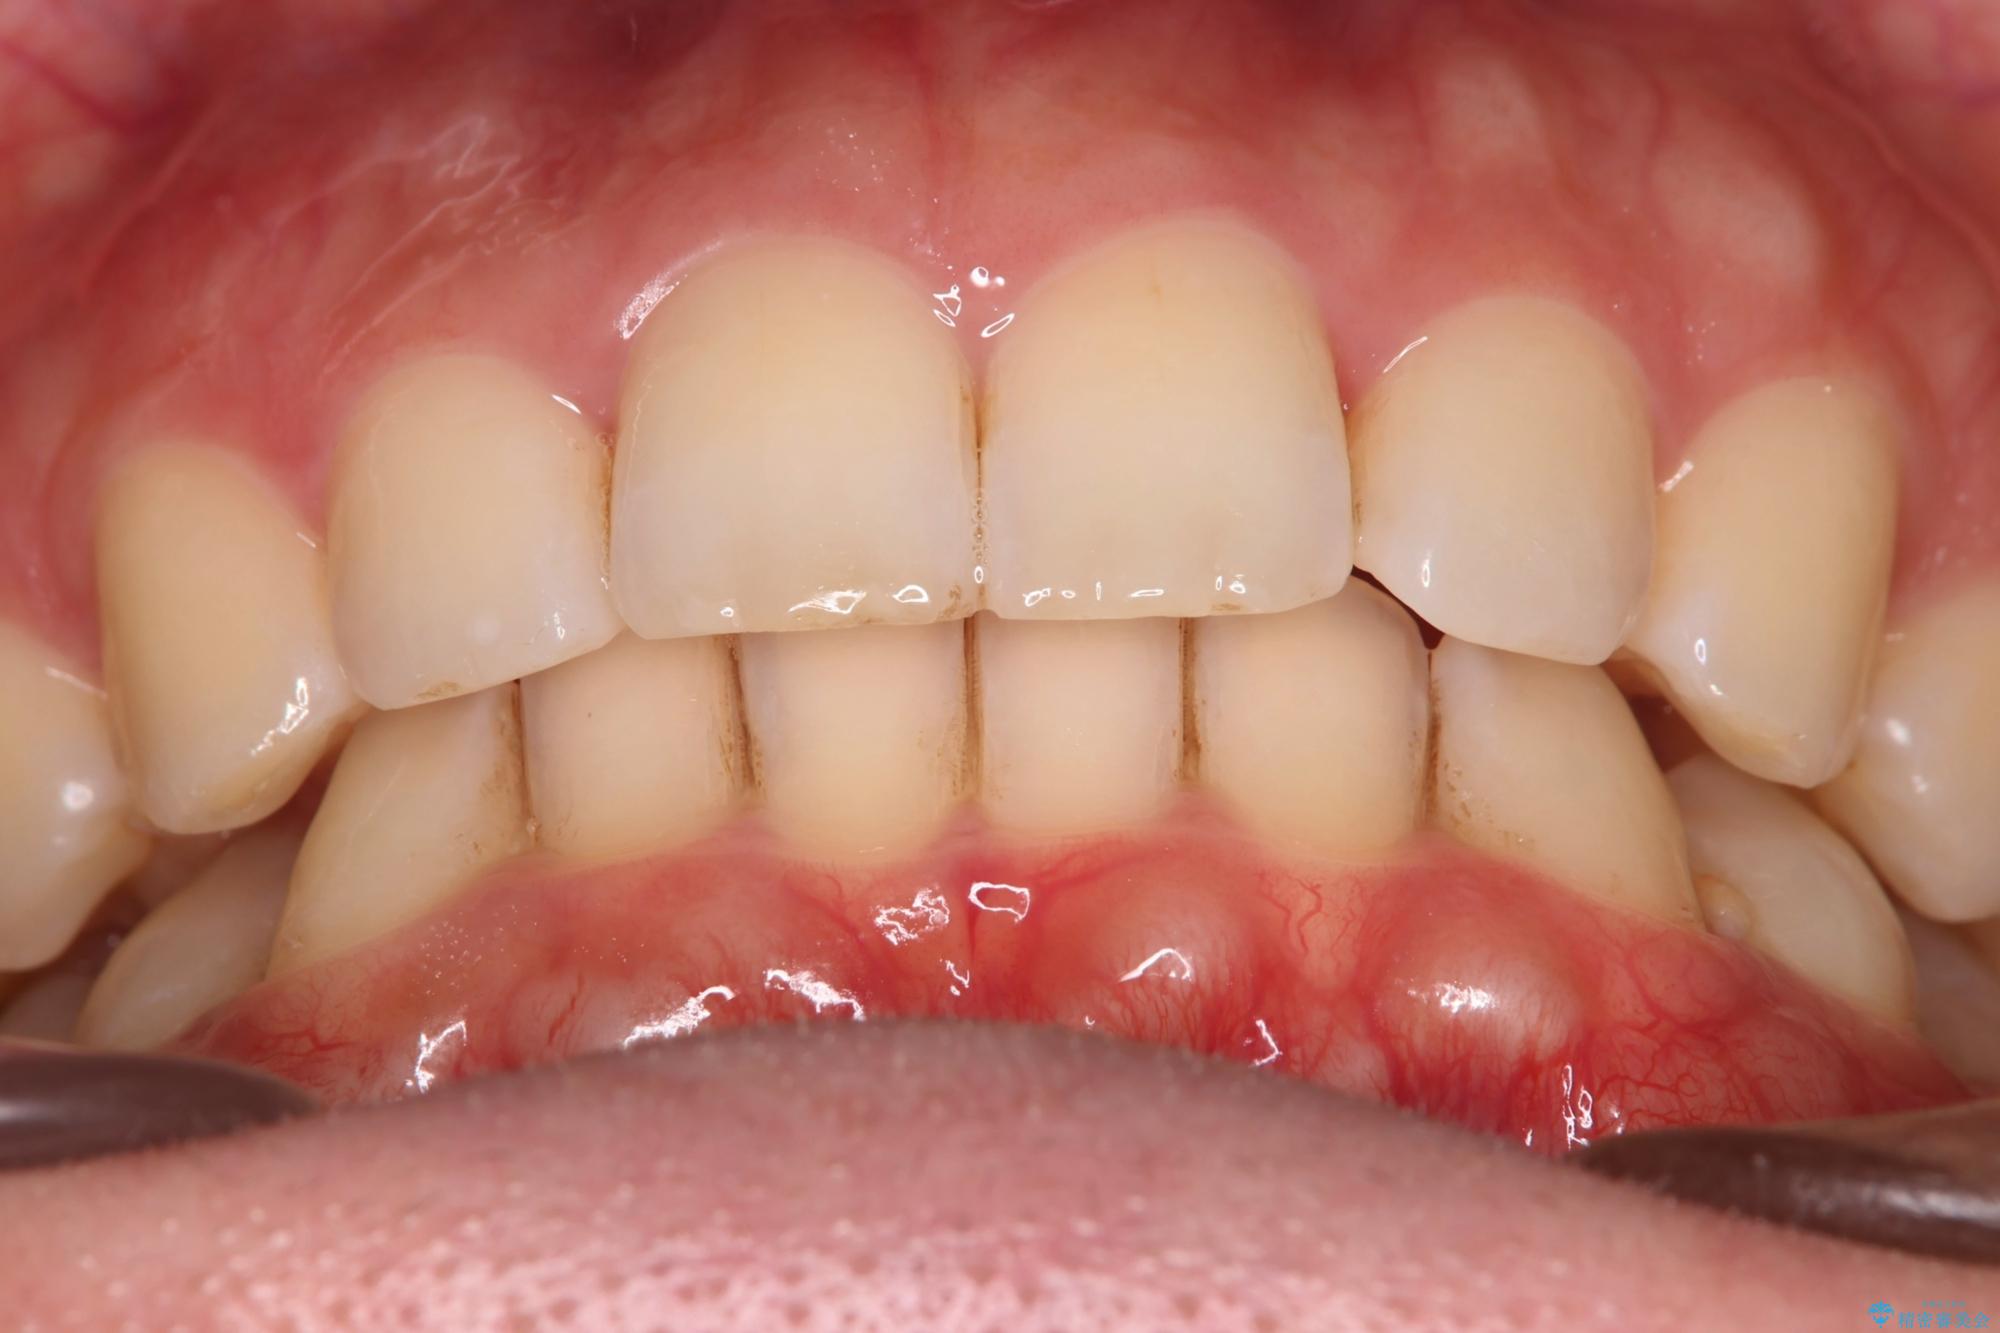

噛み合わせをよくするために、ワイヤー矯正とインビザライン矯正のどちらの期間も必要な箇所にゴム掛けを行いながら治療を行いました。

下の前歯のがたつき改善にはIPR(歯と歯の間を削る処置)を行いました。

ゴム掛けを頑張っていただいたので、噛みあわせも改善され綺麗な歯並びになりました。